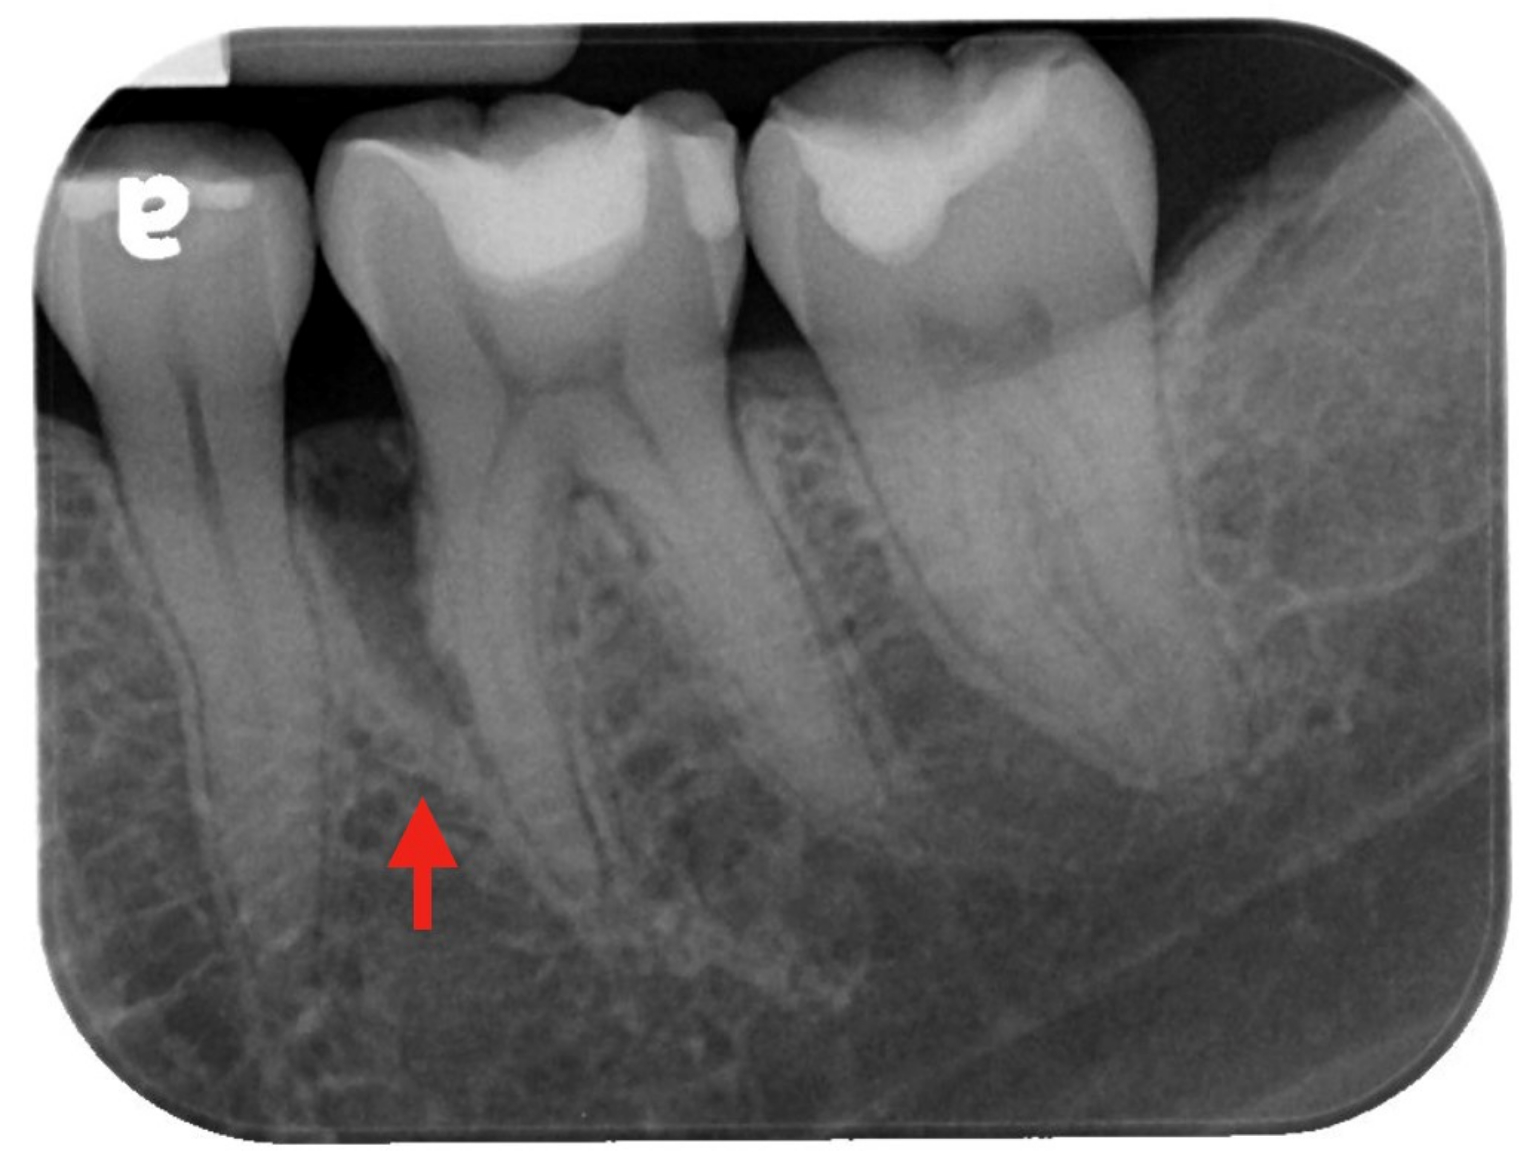

治療前:紅箭頭處可見明顯骨缺損(圖片來源/新光醫院)